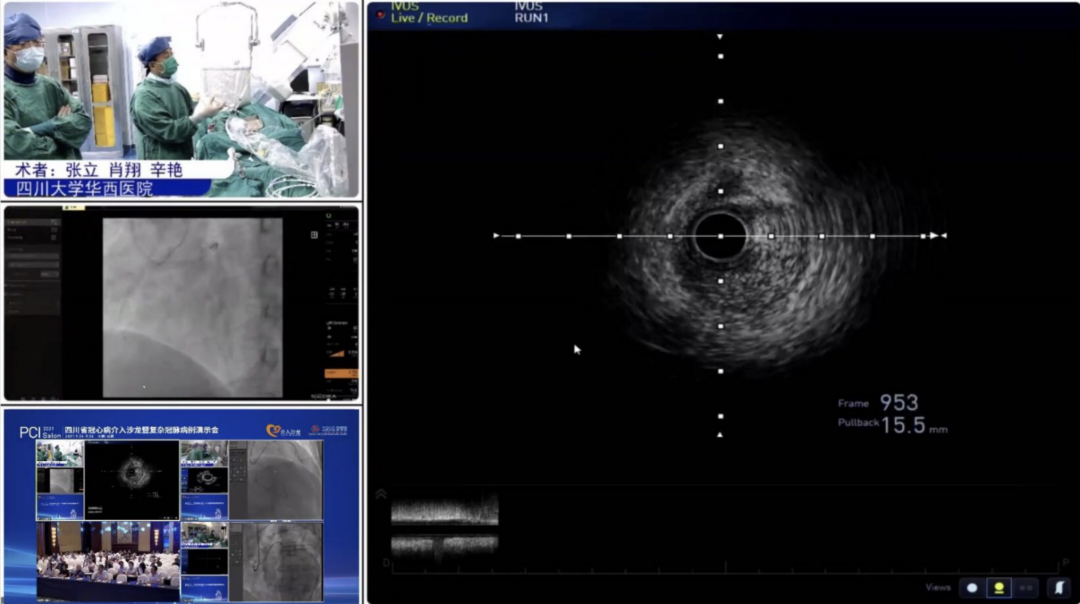

9月24日,在众多国内外冠脉介入领域专家的共同见证与支持下,四川大学华西医院冠脉影像功能培训中心的重磅成立为大会拉开了精彩的序幕。该中心集医疗、培训、教育、科研为一体,将为实现西南地区乃至全国精准化冠脉介入诊疗发展提供有力抓手。围绕冠脉腔内影像功能、CTO导丝导管的使用及选择、PCI基础及进阶培训、指引导管的临床规范化使用,聚焦冠脉介入前沿热点话题和最新技术探讨,充实紧凑的学术内容深受广大青年医师称赞。

9月25日,大会隆重开幕,大会执行主席、四川大学华西医院贺勇教授主持,大会创始人及名誉主席、四川大学华西医院心内科黄德嘉教授,北京力生心血管健康基金会管廷瑞理事长,大会主席、四川大学华西医院陈茂教授,大会创始人及名誉主席东莞康华医院贾国良教授等多位专家领导分别以线上、线下参会形式共同出席开幕式,并为大会开幕致辞。随后,来自全国多地的冠脉领域资深术者通力配合,带来了11场极具难度和技巧的复杂冠脉病例手术演示及微课讲座。同期进行的护理及技术人员论坛、冠脉腔内影像与生理学论坛、冠心病诊疗论坛、降脂治疗论坛&心衰药物进展论坛、血栓抽吸、药物球囊、愈合型支架等专题学术内容应接不暇、精彩纷呈。